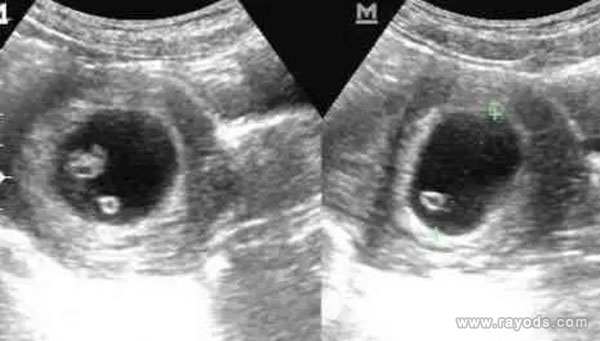

3、b超单上,孕囊看男女,男孩,孕囊长条状或茄子状;女孩,孕囊椭圆形或圆形。